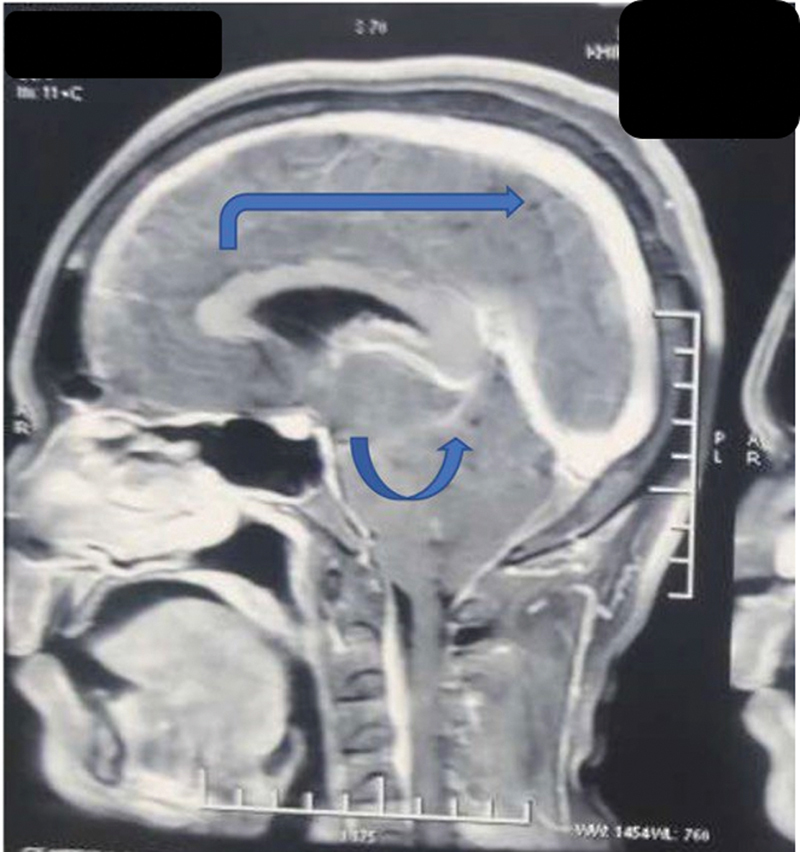

Cerebrospinal fluid (CSF) provides buoyant support to the brain and spinal cord. According to the Monroe-Kellie doctrine, confined space in the cranium causes any change in CSF volume contributing to significant intracranial pressure changes, which cause a variety of pathologies and symptoms. We, hereby, present a case of a 33-year-old gentleman who after a motorcycle road traffic accident came to us complaining of persistent headache and neck pain with subdural hematoma (SDH) like presentation, clinically and radiologically, but was reevaluated and diagnosed as traumatic intracranial hypotension and successfully managed surgically after that. Hygromas are believed to be compensatory enlargement of the subdural space due to the loss of CSF volume. The true mechanism of the development of SDH or hygroma due to intracranial hypotension is yet to be hypothesized but provisionally described by a rupture of the bridging veins by being pulled away from the dura because of the low intracranial pressure (ICP) and brain descent. Many prior cases in the literature are shown to have treated the patient with immediate burr hole and decompression of SDH, but this paradoxically worsens the patient due to further lowering of ICP. The causes of prolonged postconcussion headaches are often unidentified, of which intracranial hypotension caused by a CSF leak is potentially under-recognized. In such cases, bilateral SDH with mass effect must be ruled out of any CSF leak before attempting the lifesaving decompressive surgery, as it may paradoxically lead to further morbidity and mortality of the patient.